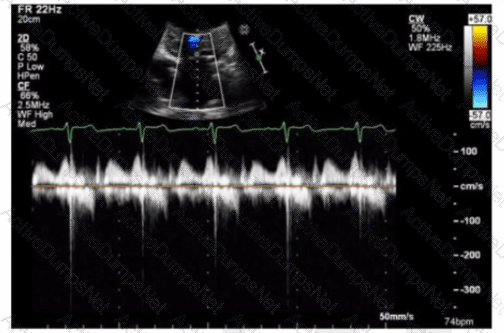

Which type of valvular lesion most commonly requires further evaluation with a non-imaging transducer?

Which finding is most consistent with this M-mode image?